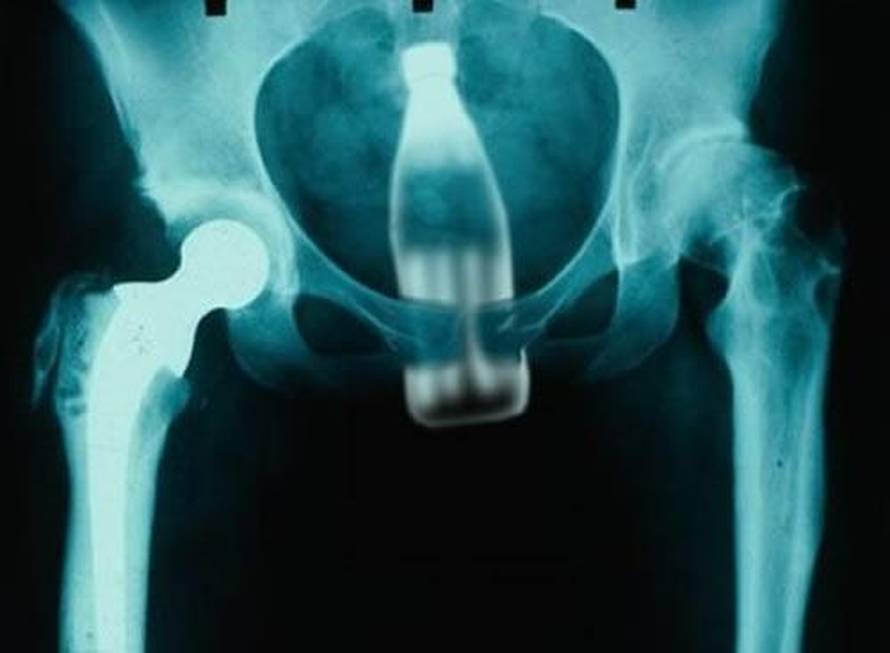

BIZARNE IGRICE: Kirurzi Kliničke bolnice Merkur u Zagrebu iz anusa maštovitih pacijenata moraju vaditi predmete koji 'pobjegnu' tijekom 'igrica'